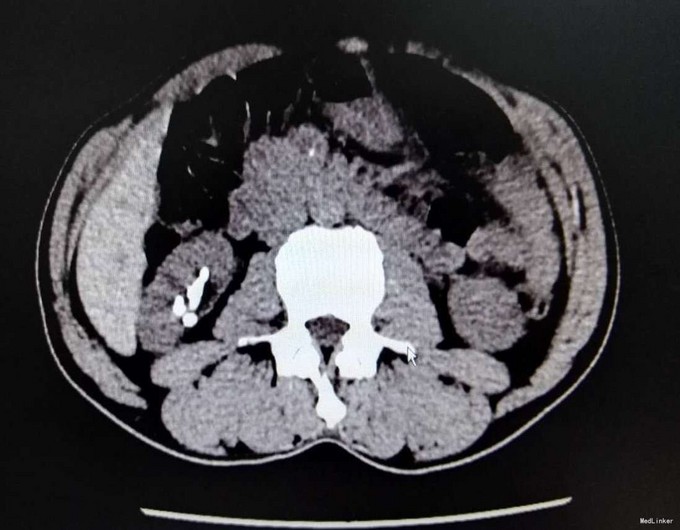

1、患者中年男性,慢性病程,既往有泌尿系结石史 2、患者2年前无明显诱因出现右侧腰部疼痛,疼痛呈放射状,阵发性,无恶心、呕吐,无尿频、尿急,尿痛,无排尿困难,无血尿、脓尿,我院门诊就诊,查KUB提示:右肾多发结石

3、查体:右肾区叩击痛(+),右侧肋脊点、肋腰点压痛(+),余查体未见明显异常 4、辅助检查:我院KUB提示:右肾多发结石,CTU平扫+增强:1、右肾多发结石,右肾下极局限性萎缩2、双肾多发囊张,3、肝多发囊肿